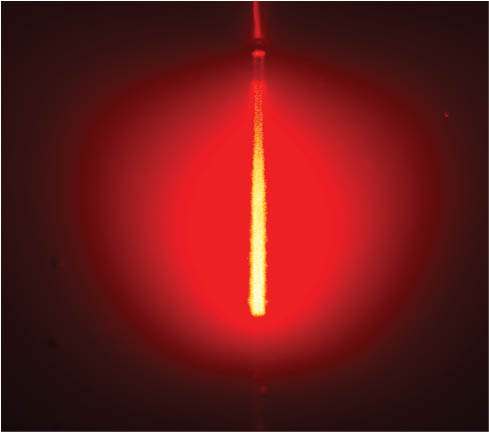

- В медицине широко используют лазерное очищение. Это новый способ избавления от вредных веществ. При облучении лазером кровеносное русло насыщается кислородом, омолаживаются клеточные элементы, разрушаются холестериновые комплексы, уменьшается риск тромбозов и тромбоэмболий. Различают два метода: чрезкожный и внутривенный. Первый не вызывает травматизации, выполняется в амбулаторных условиях. Лазерный аппарат надевают над местом расположения лучевой артерии. Лазерный пучок действует на кровяные тельца, активирует их, повышает функциональные возможности. Кровь с этого участка распространяется в артерии головы, сердца. Внутривенный метод более травматический, болезненный, требует строгих асептических условий выполнения. В вену вводится игла со световодом, происходят аналогичные реакции, как в первом случае.

Терапия лазером

Процедура проводится в больнице под контролем специалиста. Основан метод на светочувствительности кровяных телец. В вену вводят оптический волновод. Облучение клеток происходит в диапазоне красного цвета. Активируются процессы биохимического характера.

Преимущество лазерного метода: безопасность, эффективность, обширная область применения. Процедура востребована, но по стоимости обходится дорого.